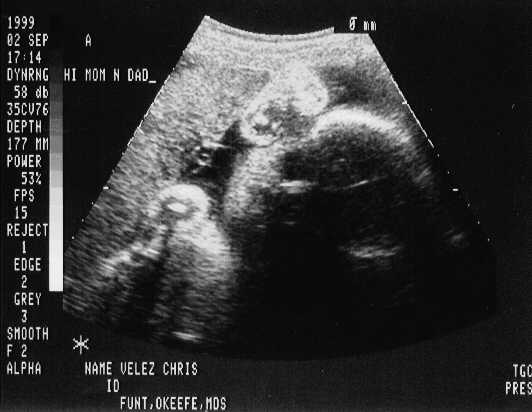

September 02, 1999 Sonograms

Kris is in her 33rd week. She can go in labor in 3 weeks!

Patrick weighs 4.6 pounds.

The doctor says he can't believe how close they are in weight. They are almost NEVER this close in size.

Patrick Joseph

sono-0902-a1.JPG - 22.3 K